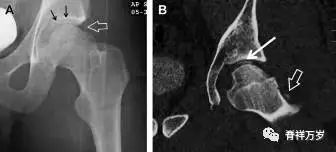

股骨颈应力性骨折

股骨颈应力性骨折在参加耐力运动的运动员中常见,且常发生在股骨颈压力侧。股骨颈基底部发现一垂直于骨皮质的线性硬化带可诊断这种类型的劳累性骨折(图 7)。

图 7 长跑运动员股骨颈应力性骨折。X 片(A)和冠状位 CT 多维重建(B)图像示穿过股骨颈内侧皮质中的透亮区(箭头),周围硬化。骨折垂直于皮质